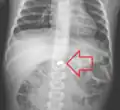

One of the most common locations for a foreign body is the alimentary tract.

It is possible for foreign bodies to enter the tract from the mouth or rectum.

Both children and adults experience problems caused by foreign objects becoming lodged within their bodies. Young children, in particular, are naturally curious and may intentionally put shiny objects, such as coins or button batteries, into their mouths. They also like to insert objects into their ear canals and nostrils.[1] The severity of a foreign body can range from unconcerning to a life-threatening emergency. For example, a coin causes local pressure on the tissue but generally is not a medical emergency to remove. A button battery, which can be a very similar size to a coin, generates hydroxide ions at the anode and causes a chemical burn in two hours.[2] An ingested button battery that is stuck in the esophagus is a medical emergency. In 2009, Avolio Luigi and Martucciello Giuseppe showed that although ingested nonmagnetic foreign bodies are likely to be passed spontaneously without consequence, ingested magnets (magnetic toys) may attract each other through children's intestinal walls and cause severe damage, such as pressure necrosis, perforation, intestinal fistulas, volvulus, and obstruction.[3]